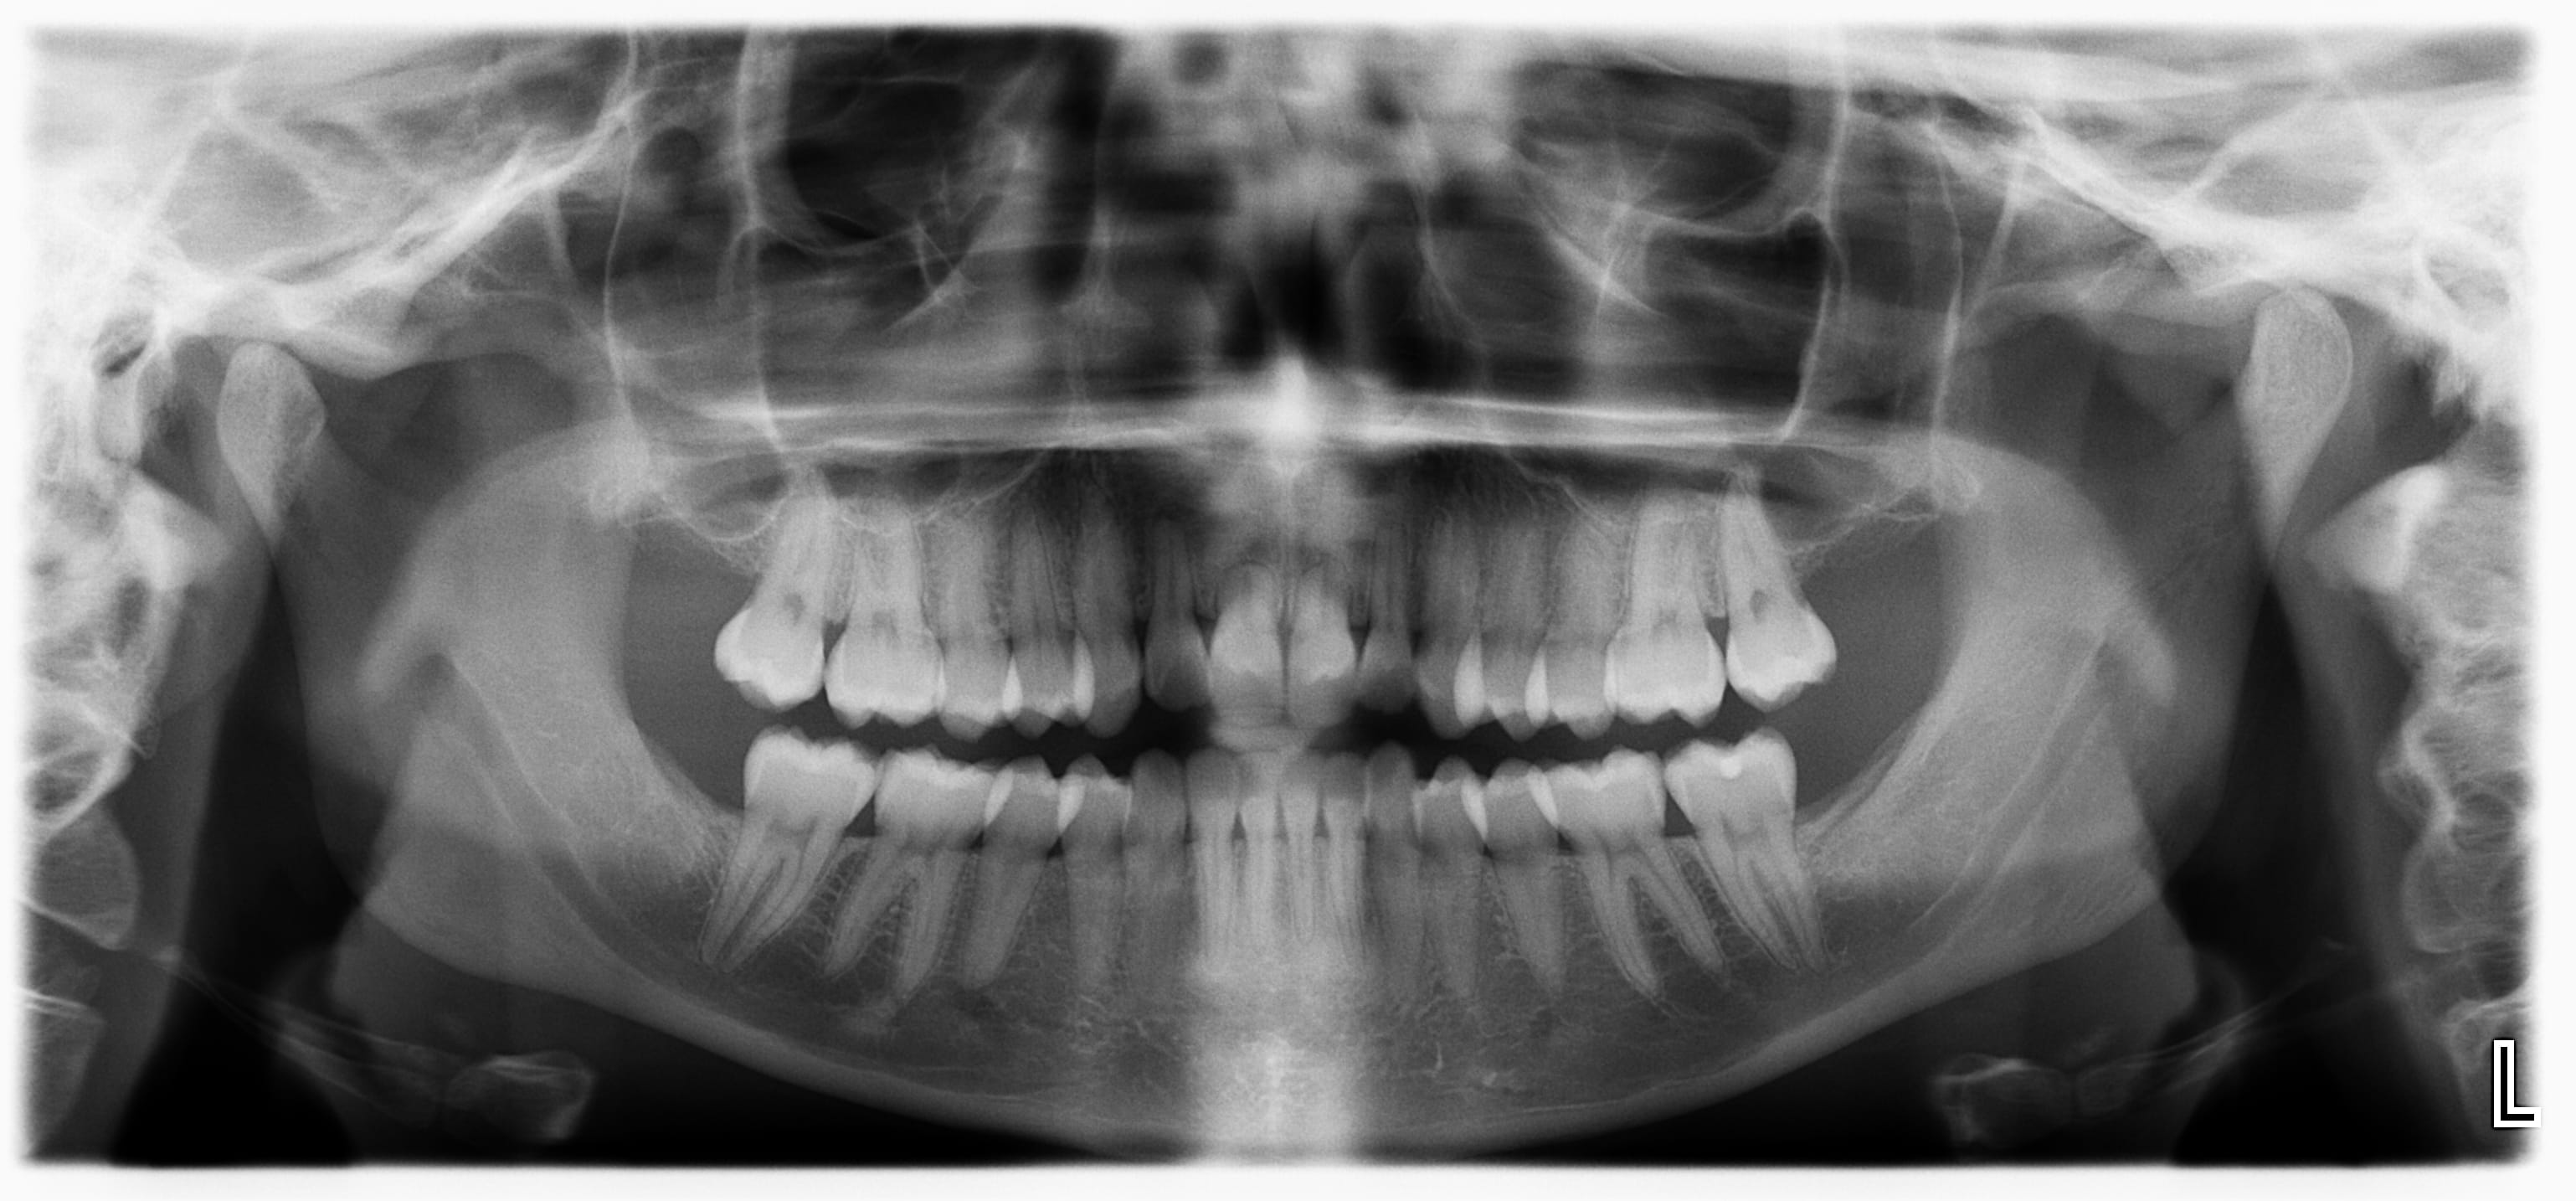

j'espère ne pas mettre trompé de rubrique , je souhait vos avis concernant 11/21 de ma patiente,

en 2 ans et demi les racines se sont considérablement rapetissées... c'est une découverte fortuite, pas de mobilité.

Effectivement, avec ce genre d'image on pense à l'ortho ... mais sur la pano 1, il y a une contention sur le bloc IC inf, le TT ortho devait être terminé (en général, les rhizalyses apparaissent assez vite, et sont objectivables en fin de TT) ?!

la premiere pano montre bien que que le tt ortho est terminé depuis longtemps.

Si les resorptions avaient été causées par l'ortho, elles auraient débutées en cours de traitement

Ce genre de resorptions radiculaires avec une zone apicale bien arrondie, je les observe quasi systématiquement chez des jeunes de moins de25 ans, qui ont toujours eu des ttt ortho quelques années auparavant. Donc on ne m'enlèvera pas de l'idée que l'ortho est en cause la dedans. C'est une image que l'on voit toujours sur plusieurs dents symétriques, et bien différente de la classique rhizalyse d'origine traumatique. Sur le cas de Yutak, les 12 et 22 sont en train de morfler aussi.

on voit sur la 2eme pano que la contention a été déposée ou décollée, en tout cas n'existe plus, avec déplacement des incisives inf visible par rapport a la pano initiale.

il y a des trucs curieux entre les 2 panos :

-reduction du cementome de 46

-migration spontanée de 43 , 44 et 34 en mésial avec redressement de l'axe

- denisté osseuse tres faible en bas de la mandibule

ces deux pano sembles venir de deux patients distincts, pas la même forme des racines des molaires , pas la même forme des sinus et des condyles , une "super cicatrisation" des extractions des dents de sagesse .......

Bravo et bien vu à Lachmar et Loulout! Effectivement les 2 panos ne sont pas les mêmes patients , désolé, c'est indépendant de ma volonté , et ce n'était pas un test!

Pour m'expliquer, la première pano n'a pas était réalisée par mes soins, par une ancienne collègue , qui a vu un patient "homonyme"au mien à une lettre près, presque le même âge, bouche très saine etc... et ma collègue s'est trompée dans l'écriture de son patient (elle a mis le nom exacte de mon patient) comme c'est un logiciel à part qui gère les panos je n'ai pas vu la petite différence d'âge etc...